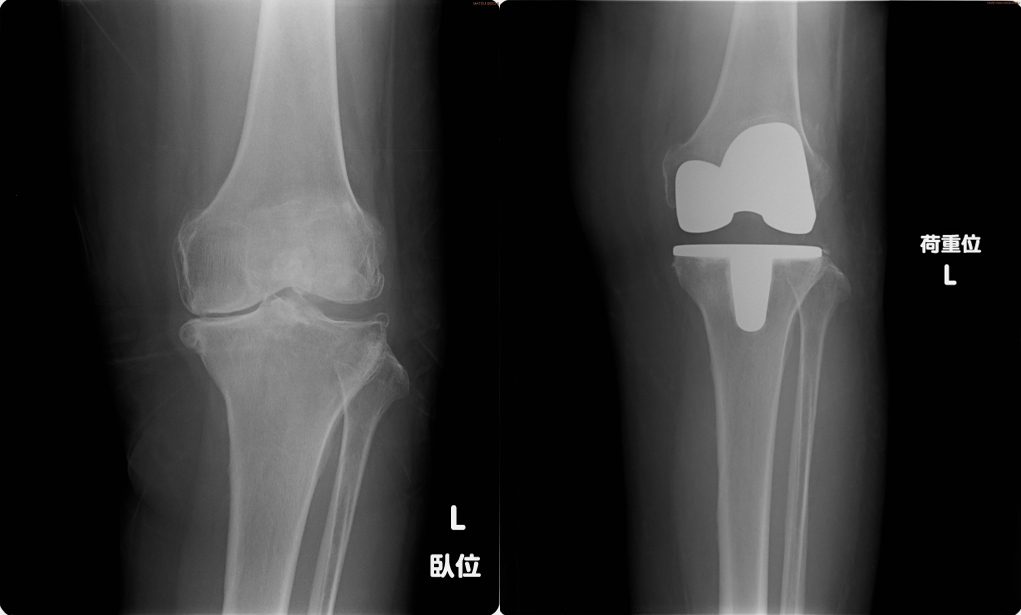

傷んだ軟骨や骨を取り除き、金属や樹脂でできた人工関節に置き換える手術です。

年間約7万件行われており、年々増加しています。膝の変形やぐらつきを改善し、痛みを和らげることができます。

患者さん一人ひとりの骨の大きさに合わせた人工関節を使用します。

【人工膝関節全置換術に用いる人工関節】

【手術前レントゲン】 【手術後レントゲン】